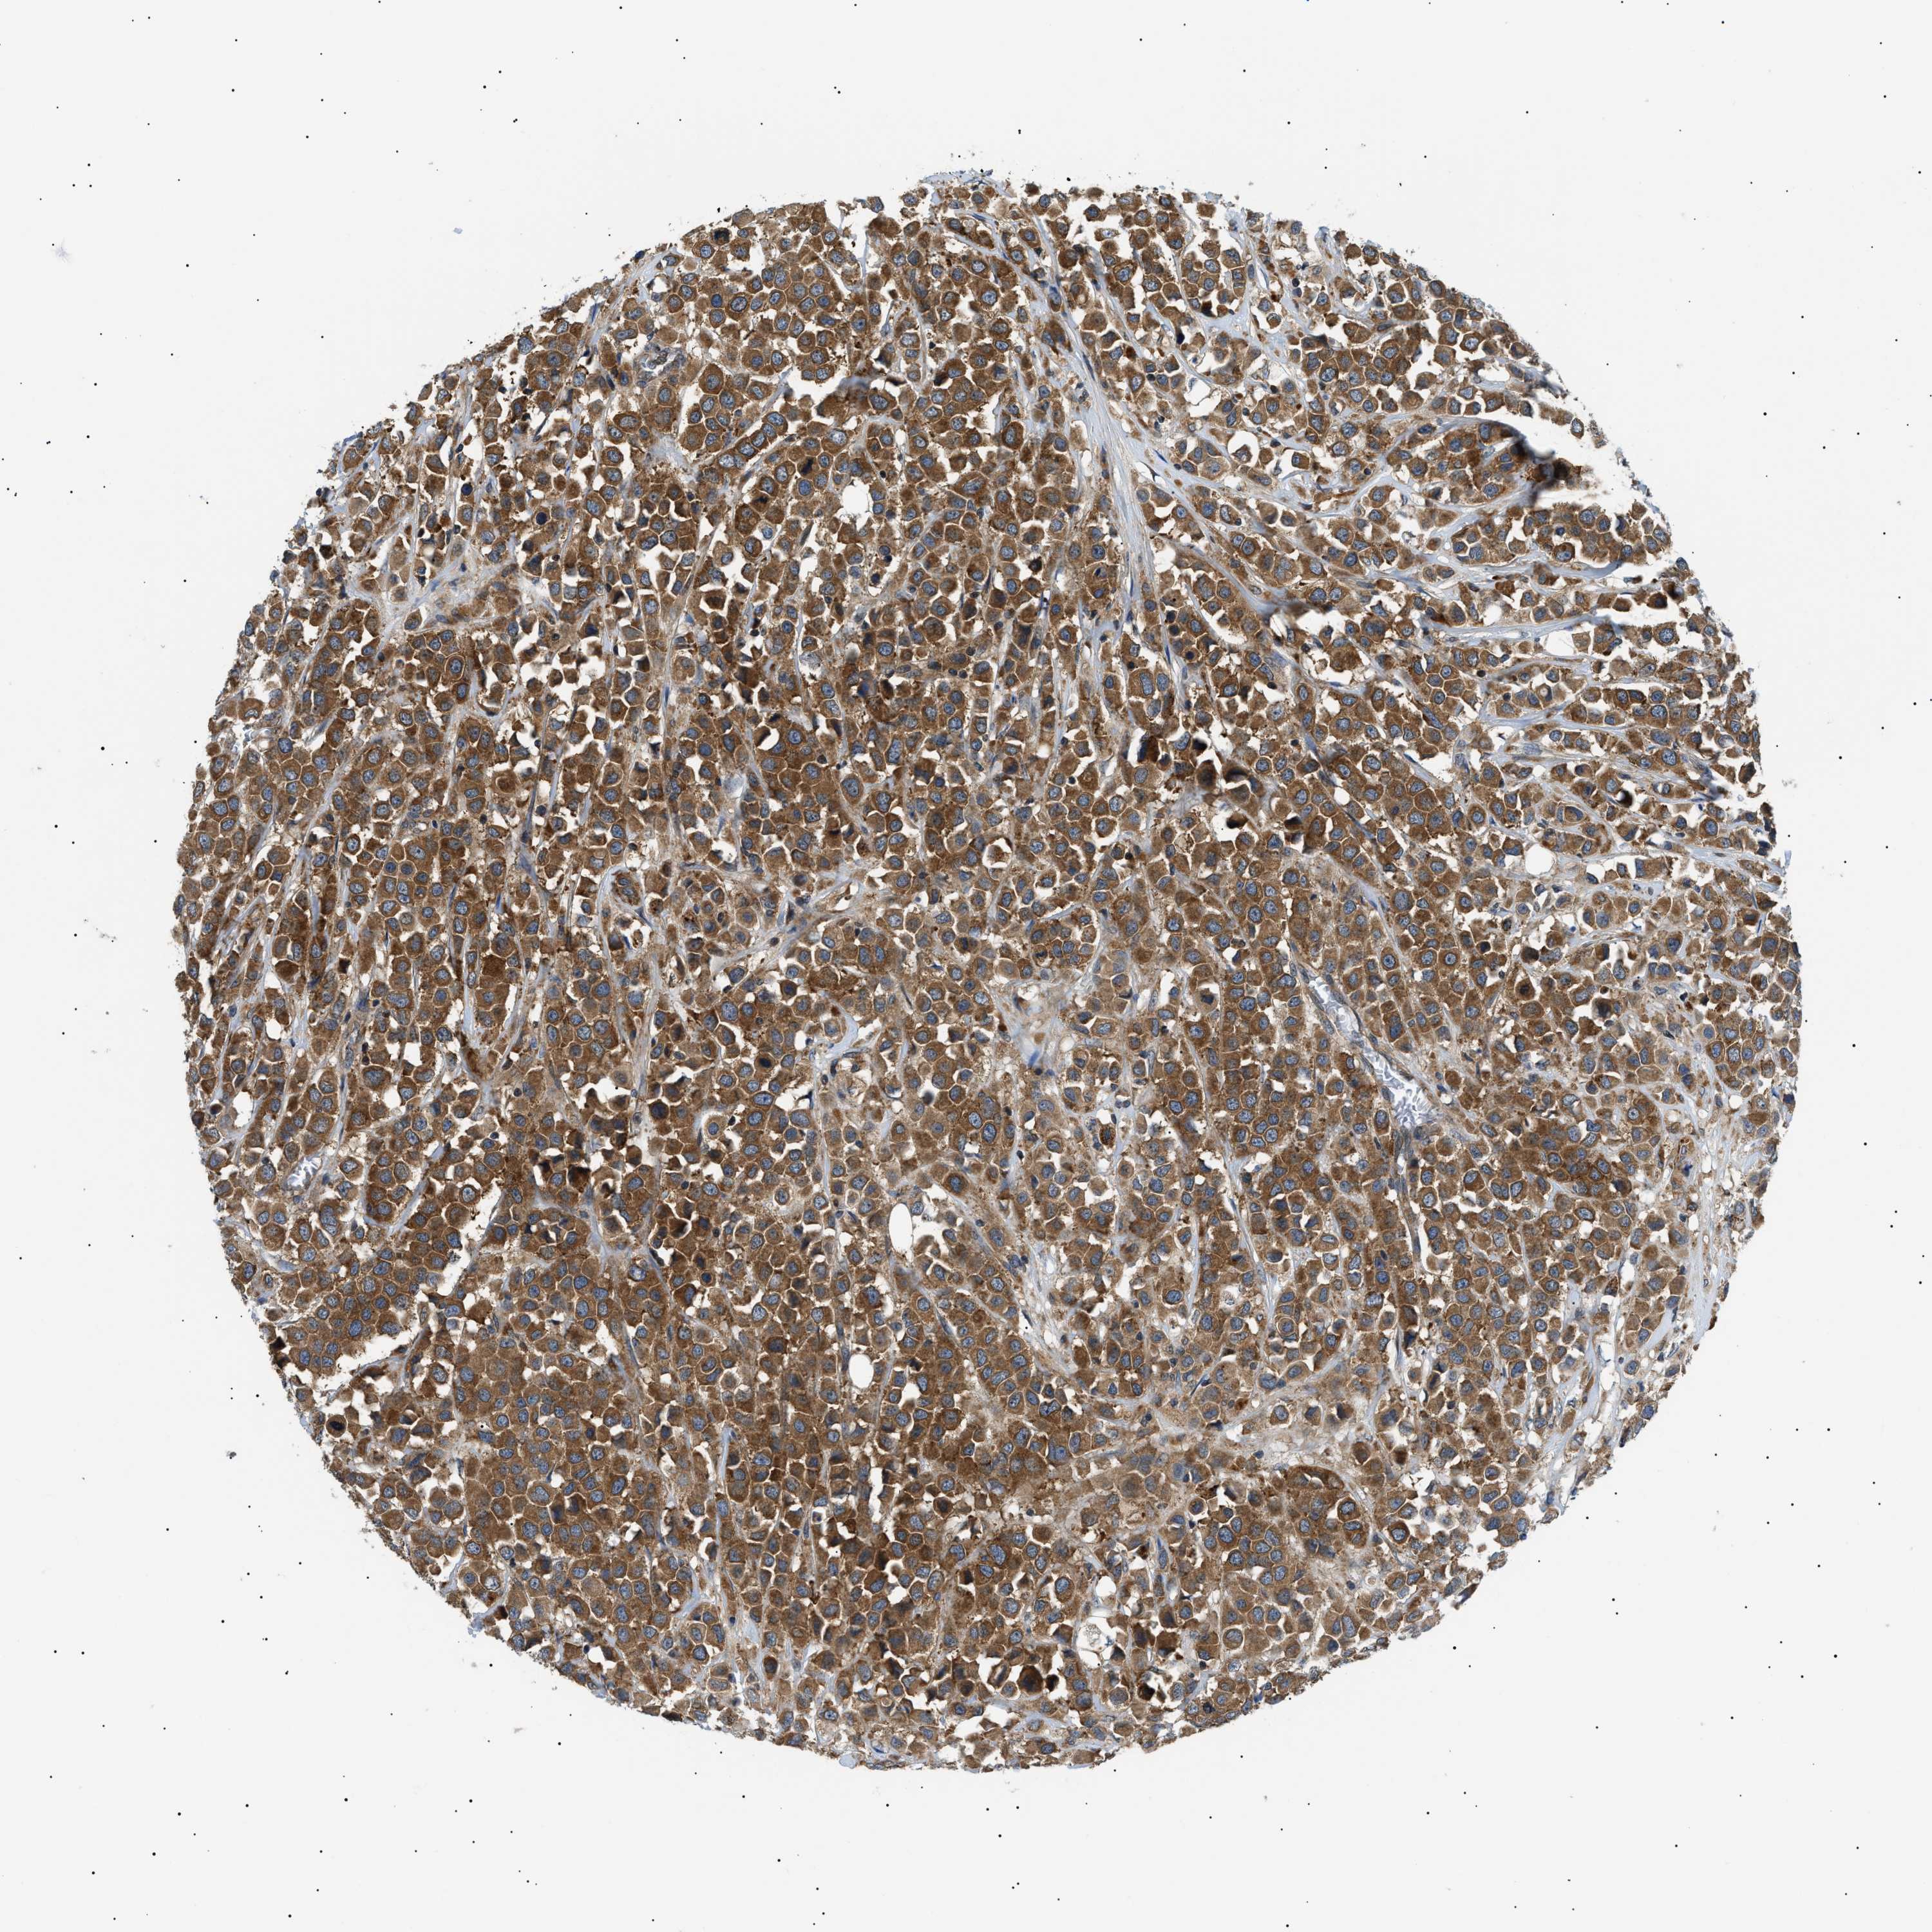

CANCER BREAST CANCER Show tissue menu

BRCA TCGA BRCA VALIDATION PROTEIN EXPRESSION